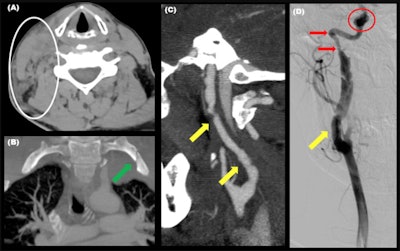

"The soft tissue ecchymosis caused by the shoulder harness can be found through the chest wall, the breast, and the neck," the authors wrote. "Blunt cerebrovascular injury is uncommon. Carotid blunt trauma has been reported. The vertebral arteries can also be involved, especially if a fracture of the transverse foramen up to C7 is present."

A cervical seat-belt sign does not necessarily increase the risk of vascular damage, they continued. Some authors suggest that in the absence of other clinical findings, the seat-belt sign does not independently justify neck CT angiography, but the guidelines adopt a liberal approach. "In a multi-institutional study, it is recommended vascular examination in the presence of at least one additional traumatic finding to the head, neck, and upper chest or a new neurological deficit."

Cervical spine injuries occur because of the oblique hyperflexion and the following hyperextension leading to ligamentous cervical injuries, which are better assessed with an MRI. The thyroid gland can also be injured by compression forces, causing a hematoma with the underlying risk of airway obstruction, requiring urgent thyroidectomy.

"Other head and neck injuries reported are cervical laryngotracheal injuries and cervical esophagus lesions (rare). These injuries are caused by compressive and rotational forces of the shoulder harness against the cervical aerodigestive tract," the researchers pointed out.

Chest wall injuries tend to align along the axis of the belt. Ribs and sternal fractures are the most common chest wall fractures, but clavicles can also be involved. Sternal fracture is better seen in the sagittal plane and the underlying anterior mediastinal hematoma is better assessed in the axial plane, and fractures of the chondrocostal union are better seen with a soft-tissue window, they stated.

Although rare, breast implant ruptures may occur. These and soft tissue injuries of the chest wall are more frequent when the shoulder harness does not lay over osseous structures.

Fractures of the chest wall are often accompanied by lung contusions and hemopneumothorax. In severe collisions, thoracic aortic rupture through the isthmus or dissection can occur. Other types of intimal injuries are pseudoaneurysms or intimal defects with no aortic contour abnormality.